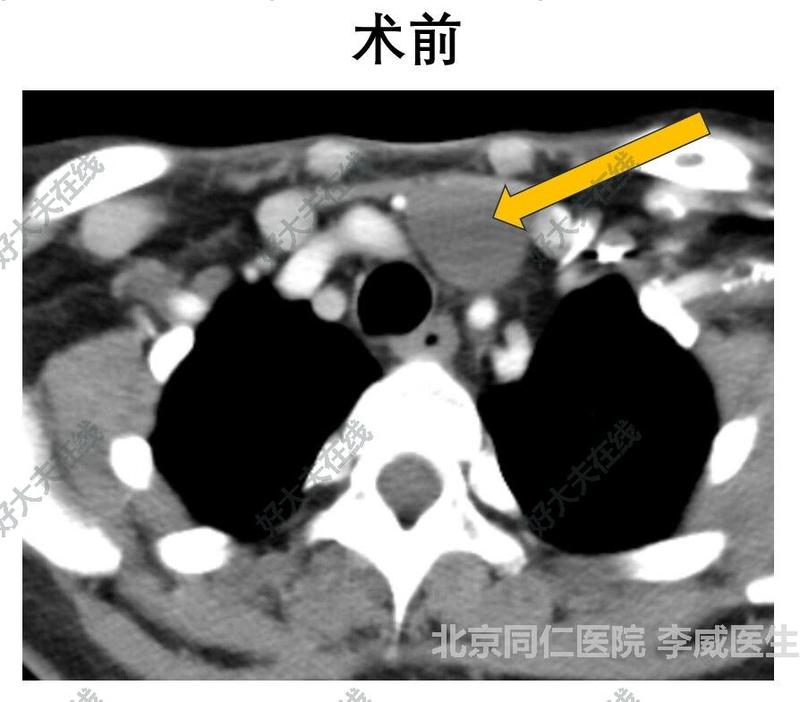

淋巴管畸形

李威醫(yī)生的科普號2023年10月07日276